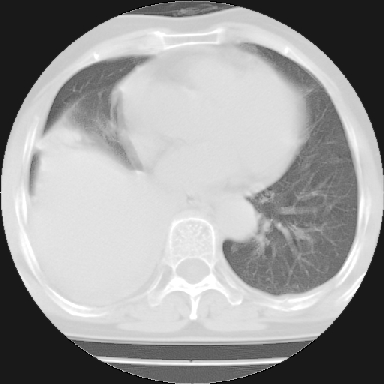

以下是引用苯小孩在2007-4-13 16:20:00的发言:[br]1、右下肺中央型肺癌并阻塞性肺不张、肺内转移、胸椎右侧附件亦有转移<横断层面第8层>.[br]2、右侧胸腔积液.

以下是引用swyyy2007在2007-4-13 15:31:00的发言:[br]右肺门下区肿块,右肺下叶支气管阻塞,右肺下叶不张,右侧大量胸腔积液,右肺中叶见结节状高密度影,边缘清,纵隔内见肿大淋巴结。首先考虑右下肺中心型肺癌伴右肺下叶不张、中叶、纵隔淋巴结转移。右侧胸腔积液。